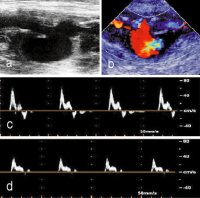

Abbildung 2a-d: Duplexsonographische Diagnostik. (a): Bypass-Ruptur mit Dehiszenz der Rupturränder im B-Mode (Pfeil); (b): Pseudoaneurysma nach gedeckter Bypass-Ruptur im Color-Mode; (c): PW-Dopplersignal proximal der Ruptur; (d): PW-Dopplersignal distal des pulsierenden Hämatoms.